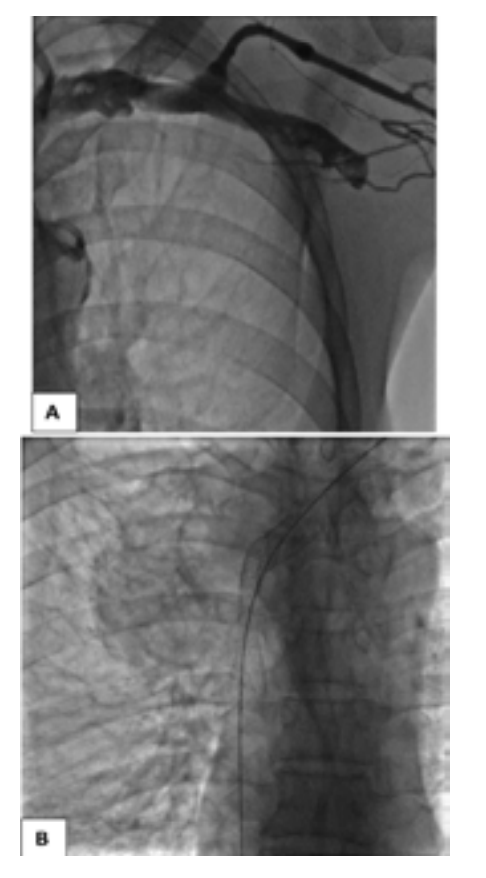

The venacavogram confirmed the absence of thrombus and revealed a stenosis in 3 cases and an occlusion in 2 cases. The stenosis/occlusion localization was the SVC in 3 cases and both SVC and the innominate venous trunk (IVT) in 2 cases.

From a therapeutic point of view, endovascular treatment of SVCS had been performed under local anesthesia. Percutaneous vena femoral approach was carried out in 2 cases. Three patients also required the use of the basilica pathway. Before stenting, the caval stenosis was dilated two or three times for almost 10 minutes by means of balloon inflation to the estimated diameter in three cases. We also routinely performed post-stent dilatation. In all procedures, a self-expanding stent had been deployed. The details regarding the stent deployed are summarized in Table 1. As an immediate follow-up, the patients experienced a quick relief of symptoms between 48-72 hours.

At one month of follow-up, a chest CT scan of control was performed. No complications occurred except in one patient: thrombosis of the stent at the first week following the treatment. According to the medical imaging, the stent was well positioned and fitted perfectly in the venous wall. The anamnesis revealed that this patient, with known psychosis, didn’t take his oral anticoagulation after being discharged. The rest of patients who underwent successful stent therapy were relieved of SVCS and their mean survival was 10 months.